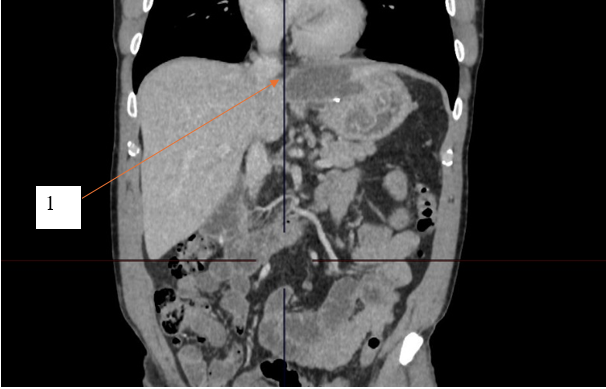

При контрольной рентгеноскопии на вторые сутки наблюдения отмечено уменьшение полости кисты, без затеков контрастного вещества, раскрытие стента удовлетворительное, до 50 % на уровне талии. Талия по центру. Течение послеоперационного периода гладкое, однако отмечалось наличие синхронного трепетания диафрагмы (singultus) вследствие раздражения нитиноловым стентом. По результатам контрольной компьютерной томографии органов брюшной полости с контрастированием, выполненной на третьи сутки после операции, стент определялся на уровне кардиального отдела желудка. Ранее выявленный жидкостной коллектор достоверно не визуализировался. Затеков ранее принятого контрастного йодсодержащего препарата за пределы стента не отмечено. Результаты контрольной компьютерной томографии представлены на рисунках 3 и 4.

Рис. 4. Компьютерная томограмма с пероральным и внутривенным контрастным усилением, пациент К., 54 года, аксиальный срез. 1 – стент на уровне кардиального отдела желудка

Fig. 4. Computed tomogram with oral and intravenous contrast enhancement, patient K., 54 years old, axial section. 1 – stent at the level of the cardiac part of the stomach